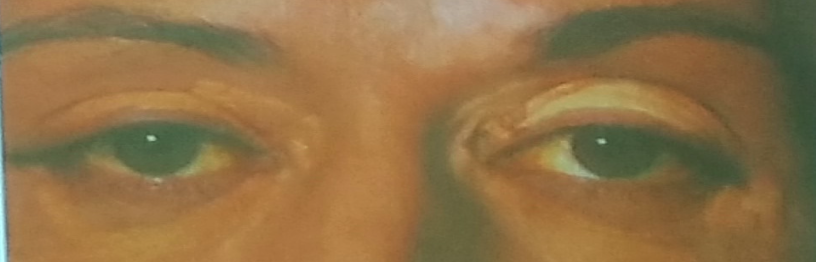

CASE 7

Q1: JAUNDICE

Q1: JAUNDICE

Q2: Mention 4 risk factors. Hemolytic Anemia. Alcohol - drugs: Paracetamol - GB stones

Q3: 4 Signs.

- Yellowish skin

Q4: Investigations. Serum Bilirubin, Urine Bilirubin, LFT

Q5: Treatment. Treat the cause

A 47 year old woman complains of generalized tiredness, low mood, altered bowel habits and more recently generalized itching. O/E she has 4 cm hepatomegaly and xanthelasma around her eyes.

Her liver function tests show:

- Total bilirubin 60 μmol/l

- AST 35 IU/l

- ALT 34 IU/l

- ALP 180 U/l

- GGT 90 U/l

- Albumin 39 g/l

- AMA titer 1:140

-

Describe the abnormalities present?

a. Increases bilirubin, ALP, GGT, AMA -

Suggest 2 possible causes of this diagnosis? Z

1- Primary Biliary Cirrhosis

2- sclerosing cholangitis